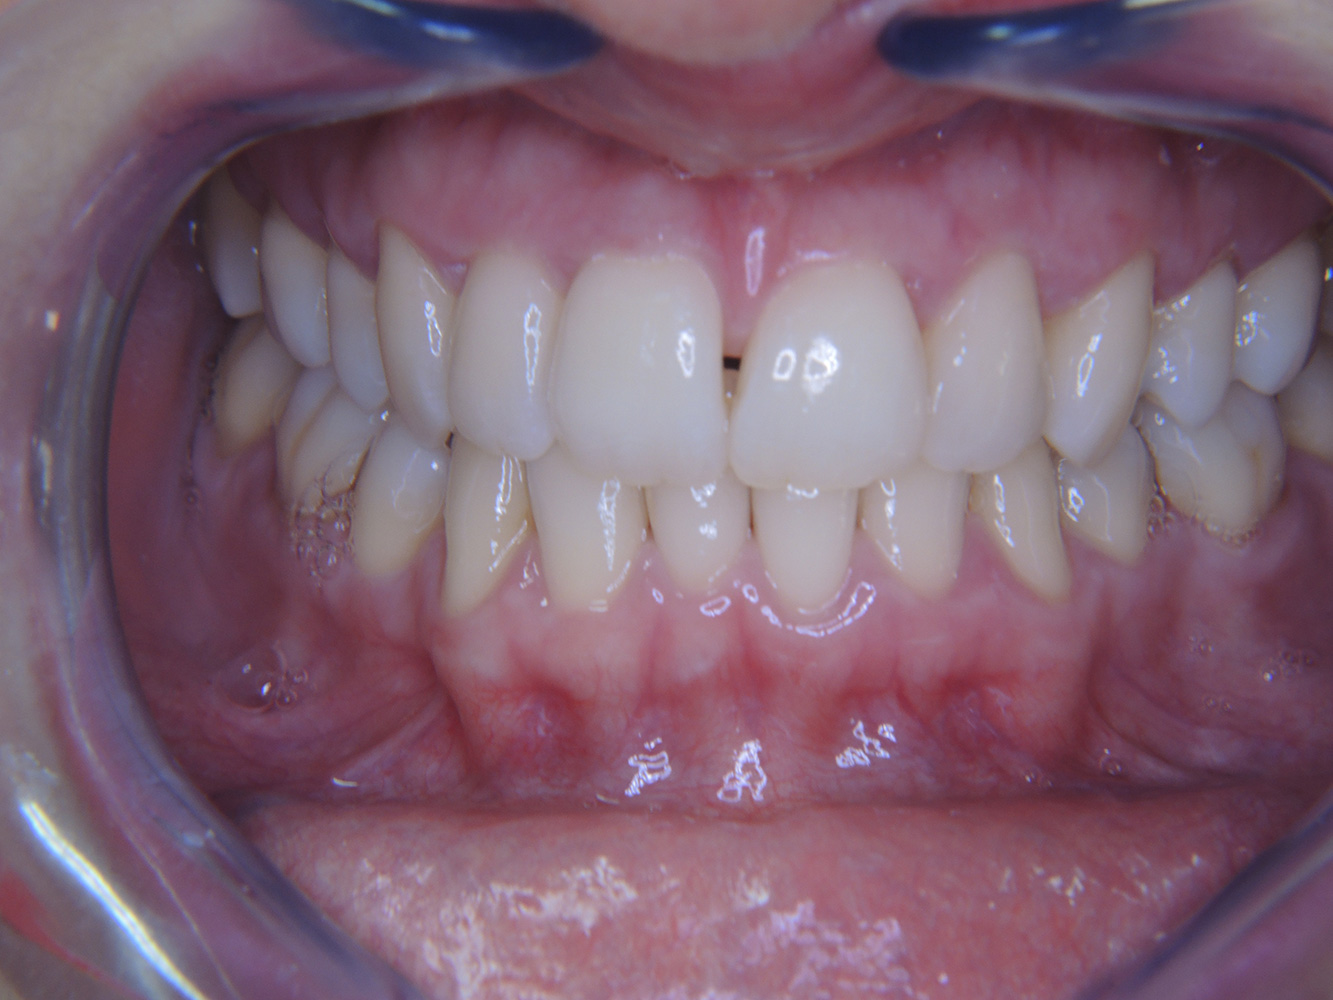

Eine 51-jährige mundgesunde Diabetikerin stellt sich zur Präventionssitzung vor. Die Blutzuckerwerte sind stabil bei einem HbA1c = 6,2%, folglich gilt sie mit dem entsprechenden Medikament Metformin (Antidiabetikum) als suffizient eingestellt. Die Patientin hat keine bestehenden Versorgungen oder orale Vorerkrankungen. Anhand der aktuellen Befunde lässt sich eine Gingivitis bei sonst stabilem parodontalem Zustand (Stage II, Grad B) feststellen. mehr Infos

Fallpräsentation: Management komplexer Zahnprothetik

Es ist längst bekannt, dass Mundgesundheit und Allgemeingesundheit in direktem Zusammenhang stehen und einen zum Teil bidirektionalen Einfluss aufeinander haben. Die Berücksichtigung beider Faktoren sind bei der Planung der oralen Prävention und Therapie der Patienten in der Zahnarztpraxis unabdingbar. Dabei ist oberstes Ziel, die Gesundheit und die Lebensqualität der Patienten sowohl aus zahnmedizinischer -und medizinischer Sicht zu erhalten. mehr Infos

Der (mund)-gesunde Patient mit Implantaten

Der 55-jährige Patient gibt in der Anamnese an, keine Allgemeinerkrankungen zu haben und keine Medikamente einzunehmen. Die Lebensgewohnheiten des Patienten sind ebenfalls unauffällig. Der Patient hat einige zahnärztliche Restaurationen und zwei Implantate (2. und 4. Quadrant). Anhand der aktuellen Befunde lässt sich eine Gingivitis bei stabilem parodontalen Zustand am reduzierten Parodont (Stadium III, Grad A) feststellen. mehr Infos

Der gesunde Patient mit parodontaler Vorerkrankung & Periimplantitis

Ein 52-jähriger Patient stellt sich zur Präventionssitzung vor. Der Patient hat keine Allgemeinerkrankungen und nimmt keine Medikamente ein. Er hat verschiedene zahnärztliche Versorgungen und zudem zwei aktive kariöse Läsionen. Außerdem verfügt der Patient über vier Implantate (2., 3. und 4. Quadrant). Es zeigt sich eine parodontale Vorerkrankung (Stadium IV, Grad B). Derzeit herrschen stabile parodontale Verhältnisse, lediglich am Implantat regio 36 zeigen sich Sondierungstiefen (ST) von 5 mm. Zudem lässt sich eine Gingivitis feststellen. mehr Infos

Der Diabetiker mit Parodontitis

Dieser Fallbericht eines 52-jährigen Mannes mit Typ-2-Diabetes und Parodontitis hebt hervor, wie durch individuelle Vorsorgemaßnahmen, die Gesundheit des Zahnhalteapparates erhalten bzw. das Fortschreiten der Erkrankung kontrolliert werden kann. mehr Infos

Der 28-jährige Raucher mit Zahnerosionen

Dieser Fallbericht eines 28-jährigen Rauchers mit Zahnerosionen zeigt die Bedeutung personalisierter Patientenprofile. Er unterstreicht die Notwendigkeit, sowohl die Mundgesundheit als auch die allgemeine Gesundheit zu berücksichtigen, um Erkrankungen der Zähne bzw. des Zahnhalteapparates effektiv zu verhindern. mehr Infos

Der Endokarditis-Patient mit aktiven Kariesläsionen

Der Patient ist 39 Jahre mit Z.n. Herzklappenersatz wegen Klappenfehlers und Endokarditis. Als Antikoagulans (Gerinnungshemmer) wird regelmäßig ASS 100 eingenommen. Aus dem Bereich Lebensstil ist die Ernährungsweise als kariesfördernd einzustufen, da mit hoher Regelmäßigkeit zuckerhaltige Lebensmittel sowie sechs bis sieben Mahlzeiten täglich verzehrt werden. Die Mundgesundheit des Patienten zeigt ein mittleres Kariesrisiko mit aktiven Läsionen. Das Parodontitisrisiko ist niedrig, es besteht eine Gingivitis. Es ergeben sich folgende Empfehlungen für die Prophylaxebehandlung. mehr Infos

Die gesunde Patientin mit parodontaler Vorerkrankung

Die 68-jährige Patientin hat keine zahnmedizinisch relevanten allgemeingesundheitlichen Vorerkrankungen oder Medikation, auch aus dem Lebensstil ergibt sich kein besonderes Risiko. Die Patientin hat zwei Implantate (3. Quadrant, seit fünf Jahren) sowie eine parodontale Vorerkrankung (Parodontitis Stadium IV, Grad B) mit Zahnverlust. Derzeit zeigen sich stabile parodontale Verhältnisse. Für die Prophylaxesitzung ergeben sich vier Empfehlungen in den Bereichen Anamnese/Befund, Motivation/Instruktion, der Wahl der geeigneten Instrumente und für Resümee/Folgetermin. mehr Infos

NIWOP – No Implantology without Periodontology

Der Transplantationspatient mit Gingivawucherungen

Ein 71-jähriger Patient mit Z.n. Nierentransplantation und Hypertonie (Bluthochdruck) stellt sich vor. Bedingt durch die Krankengeschichte ist eine Dauermedikation mit Cyclosporin, zur Unterdrückung der Immunabwehr, und Amlodipin, zur Blutdrucksenkung, erforderlich. Außerdem berichtet der Patient über empfindliches Zahnfleisch und Zahnfleischbluten. Aus mundgesundheitlicher Sicht zeigt sich ein saniertes Gebiss mit acht fehlenden Zähnen, ausgeprägte Gingivawucherungen, eine Parodontitis Stadium II, Grad B mit aktiven Taschen und eine initiale Wurzelkaries an Zahn 22. In der Kariesrisikoabschätzung wird ein mittleres Kariesrisiko (API 60) festgestellt. Für die Prophylaxesitzung lassen sich folgende Behandlungsempfehlungen ableiten. mehr Infos